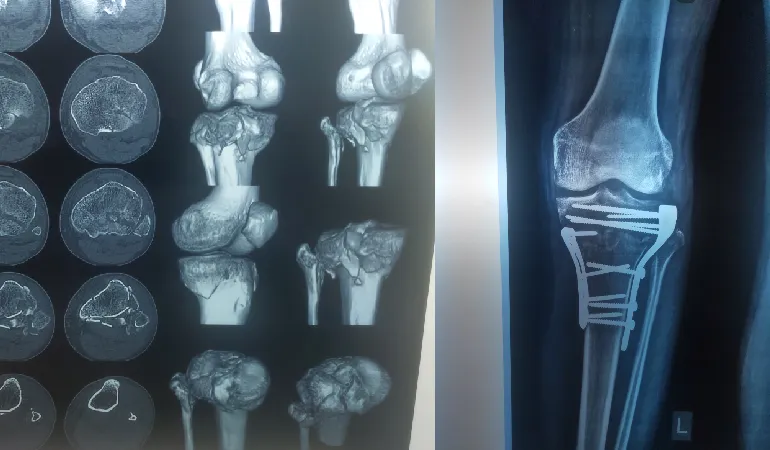

His clinical journey is defined by an extraordinary milestone of performing more than 10,000 successful surgeries. This vast experience ranges from routine fracture care to some of the most complex joint replacements and arthroscopic procedures in the region. Dr. Shah’s practice at Vedant Hospital, Gota, is built on the pillars of precision, ethical practice, and deep-rooted compassion.